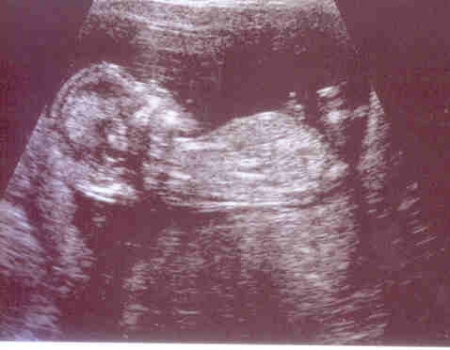

Plod o velikosti 81 mm ve 13. týdnu těhotenství (12+5)

Autoři: Texty na základě zdroje www.babyonline.cz, vlastní praxe a znalostí zpracovala MUDr. Jarmila Halová, doplnil a upravil MUDr. Ondřej Šimetka, přednosta Porodnicko-gynekologické kliniky FN Ostrava, kde byly rovněž pořízeny ultrazvukové snímky, autor: MUDr. M. Pětroš. Poslední korekturu v srpnu 2024 provedla: MUDr. Veronika Ťápalová (Gynekologicko-porodnická klinika LF MU a FN Brno).